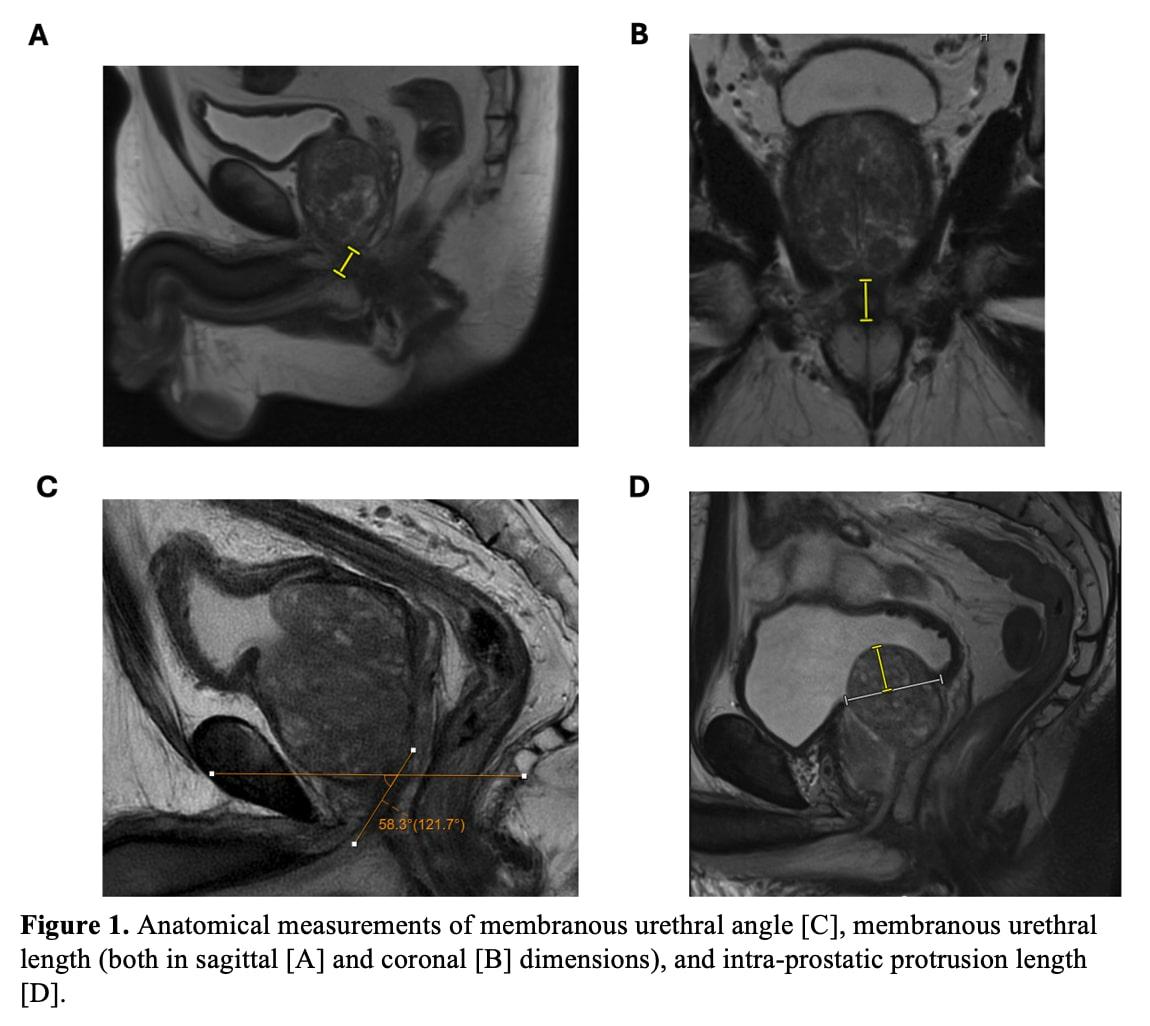

BACKGROUND: Anatomical dimensions of the prostate and membranous urethra are well-established predictors of urinary incontinence following robotic prostatectomy. However, their role in predicting incontinence after holmium laser enucleation of the prostate (HoLEP) remains underexplored. This study evaluated the predictive value of preoperative anatomical measurements, including membranous urethral length (MUL), membranous urethral angle (MUA), levator ani thickness (LAT), and intravesical prostatic protrusion length (IPPL), in assessing early postoperative urinary incontinence following HoLEP. METHODS: We retrospectively reviewed 122 patients who underwent HoLEP from April 2019 to June 2022 with preoperative MRI. Anatomical features including coronal and sagittal MUL, MUA, LAT, and IPPL were assessed. Urinary incontinence, defined as the use of ≥1 pad per day, was evaluated at 1-, 3-, and 6-months postoperatively. Logistic regression analyses were adjusted for age, BMI, post-void residual, preoperative incontinence, and PSA, and ROC curves were constructed to assess the discriminatory utility of MRI anatomical measurements. RESULTS: Increasing MUL was significantly associated with reduced incontinence risk at 1 month (coronal MUL: OR, 0.85; 95% CI, 0.75-0.96; P = 0.01; sagittal MUL: OR, 0.89; 95% CI, 0.79-0.99; P = 0.046). No significant associations were found for MUA, LAT, or IPPL. ROC analysis of averaged coronal and sagittal MUL revealed moderate discriminatory power (AUC: 0.644), with a threshold of 14 mm identified via the Youden index. Individuals with an MUL < 14 mm had nearly 4-fold increased odds of incontinence at 1 month (OR 3.835, 95% CI, 1.516-9.703; P = 0.005). CONCLUSIONS: Preoperative MUL measurement provides a practical, imaging-based method to predict early postoperative incontinence following HoLEP. Incorporating MUL into preoperative evaluations may improve risk stratification, patient counseling, and perioperative management.